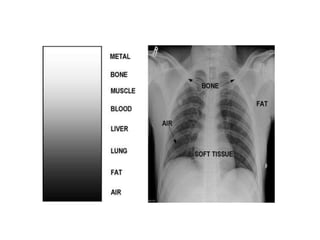

• Shades of gray on film are a

representation of the different

densities of the anatomic tissues

through which the xrays have

passed

• Tissues with greater density will absorb more of the xray so less of the

beam reaches the film plate. The resultant image is therefore lighter.

Tissues with less density will allow more x ray to reach the film so it will

be darker. This is called radiodensity and is determined by: thickness

and composition of structure.

• Air: black eg: trachea, lungs, stomach, digestive tract.

• Fat: gray black eg: subcutaneously along muscle sheaths ; around

viscera.

• Water: gray eg: muscles, nerves, tendons, ligaments, vessels

(all of these structures have the same density and therefore are hard

to distinguish on plain x rays.)

• Bone: gray/white. (Calcium with higher atomic number absorbs higher

proportions of x-rays resulting in less crystal formation in the film –

Radioopaque appearance of bone

• Contrast medium: white outline.

• Heavy metals: white solid.